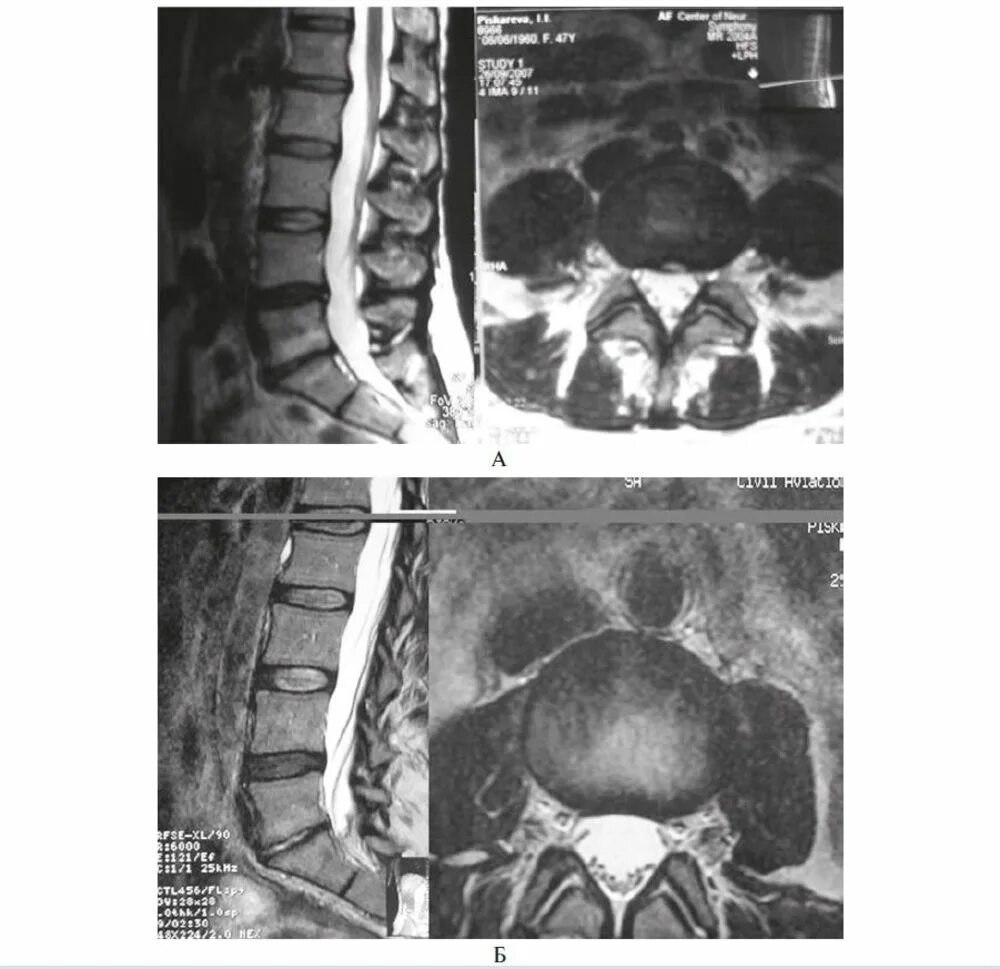

Спондилоартроз кт